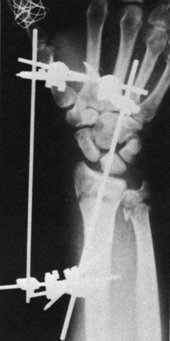

The goals of medical management of a fracture are to reduce pain and align the fracture for proper healing.18 The fracture can be aligned with or without surgery. The process of manually realigning (sometimes using traction devices) and then casting a fracture is termed closed reduction. The open reduction is a surgical procedure that is used to internally fixate the fracture site. Internal fixation is performed with the use of orthopedic nails, screws, pins, rods, or plates. When external fixation is used to align or reduce a fracture, the fixator device is attached with pins or wire, which is inserted through the soft tissues and into the bone (Figure 22-2). This device usually involves the use of screws and rods that are removed after the fracture has healed. The skin around placement sites of the rods or screws must be kept clean to prevent infection (Table 22-1).

image

FIGURE 22-2 External fixator in place to maintain reduction.

(From Hunter, J., Mackin, E., & Callahan, A. (Eds.). (1995). Rehabilitation of the Hand: Surgery and Therapy, 4th ed. St. Louis, MO: Mosby.)